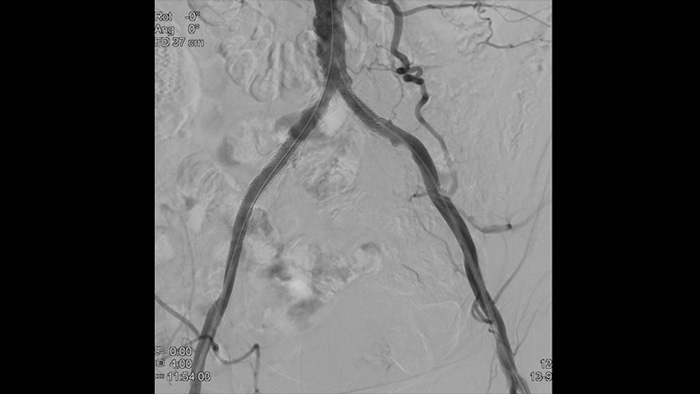

SmartCT Roadmapは、ライブ3D画像オーバーレイ機能を備え、画像をセグメンテーションして対象となる血管と病変を強調できます。SmartCT Roadmapでは血管全体、セグメンテーションされた血管、アノテーションの3D再構成画像をライブの透視像と併せてオーバーレイします。これにより3D画像の透明度とコントラストが得られ、詳細部の視認性が向上します。

血管の高精細画像は血管の細部まで鮮やかに捉えるため、正確な治療戦略、ナビゲーション、フォローアップをサポートします。